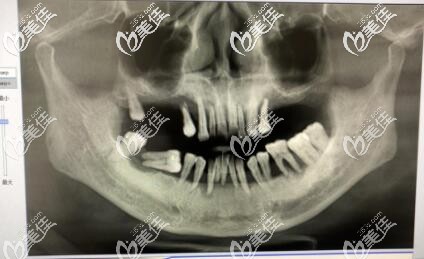

李孟奇院长指出:患有牙周炎是不可以做种植牙的,因为很容易导致种植牙失败,一定要等牙周炎治疗好了,在去医院做种植牙。牙周炎病患者常会导致牙龈萎缩,形成牙周袋,使得牙根暴露,牙齿松动,在这样的牙齿上再加上瓷冠更会增加牙周负担,加重牙周炎病。如果要做,必须在牙周病控制后再进行。

牙周炎后的义齿修复必须建立在健康的牙周基础之上。且必须清除所有与牙周炎有关的病原刺激,包括菌斑、牙石等,建立起有效的菌斑控制手段,消除或控制牙周袋,防止牙周病再度复发,否则即使种上再好的种植体,也是徒劳无功。